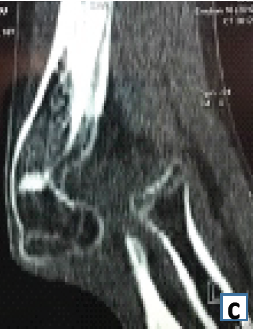

Neglected Anterior Elbow Dislocation without Fracture: An Unusual Case in an Adolescent

Gueye Alioune Badara , Mouhamadou Moustapha Niane , Kalifa Ababacar Faye , Yacine Sock , Charles Valerie Alain Kikpe

………………………………p.182-184